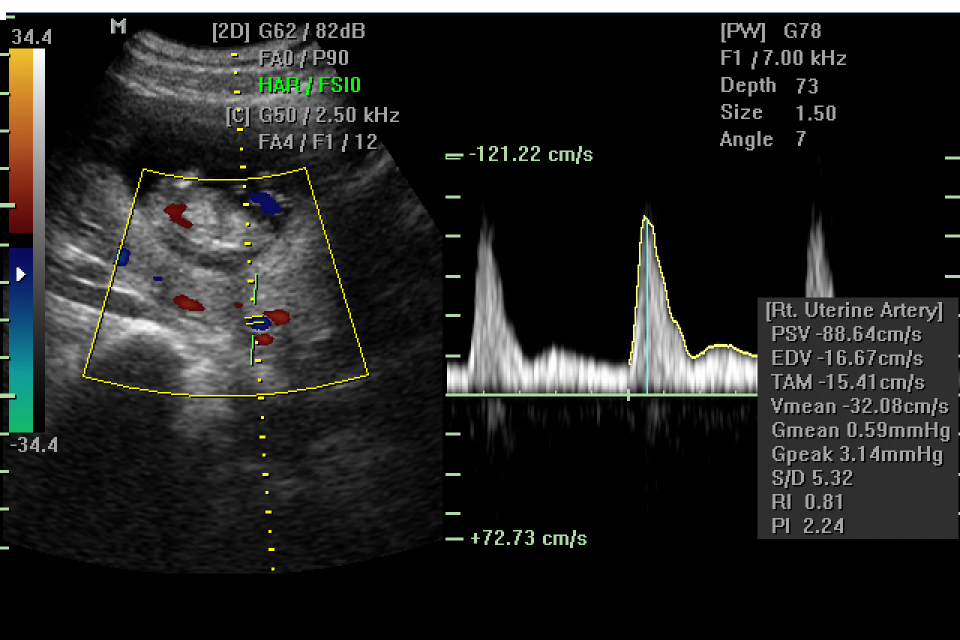

ECOGRAFIA RIPRODUTTIVA